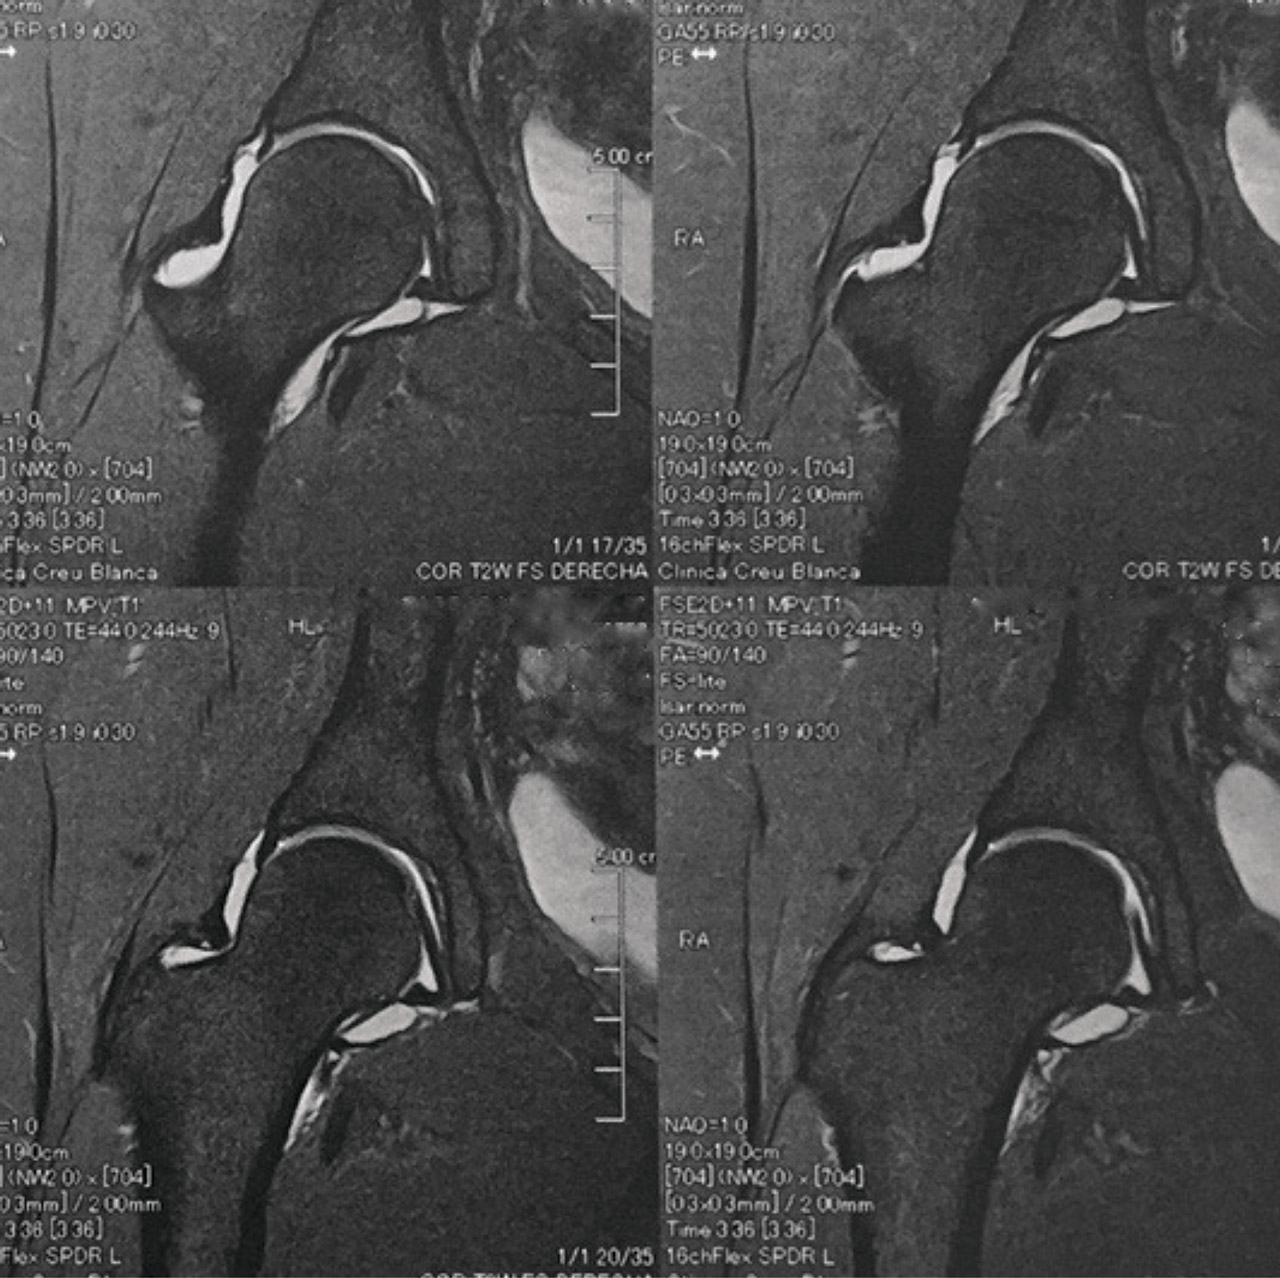

El estudio de imagen mostraba una ausencia de deformidad ósea y no se apreciaron lesiones en la radiografía ni la artrorresonancia (Figuras 1 y 2). El ángulo alfa en la imagen axial izquierda era de 49,6°, mientras que el ángulo de cobertura acetabular de Wiberg era de 34,6°.

Las pruebas de imagen no muestran alteraciones en forma de deformidad de tipo CAM ni PINCER (tanto en radiografías como en resonancia). El ángulo alfa en la proyección axial era de 38,2° y el ángulo Wiberg de 34,5° (Figura 5). Asimismo, el estudio mediante artrorresonancia no evidenció lesiones de labrum ni deformidades del tipo AFA (Figura 6).